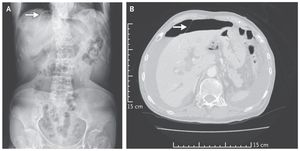

An 87-year-old woman with a history of hypertension and peptic ulcer disease presented to the emergency department with a 3-day history of abdominal distention, pain in the epigastrium, and watery diarrhea. She had hypotension (blood pressure of 78/49 mm Hg), and diffuse abdominal tenderness with guarding was observed on physical examination. An abdominal radiograph that was obtained with the patient in a supine position revealed the falciform ligament sign (Panel A, arrow) — a radiographic sign of pneumoperitoneum. The falciform ligament connects the liver to the anterior abdominal wall. When surrounded by intraperitoneal free air, the falciform ligament may be seen as a vertical band of soft tissue on a computed tomographic scan of the abdomen (Panel B, arrow). An emergency laparotomy was performed, and the diagnosis of a bowel perforation was confirmed; a 2-cm perforation in the duodenum was repaired. The patient was discharged from the hospital 22 days later and recovered well. Po-Chen Chou, M.D. Yu-Jang Su, M.D. Mackay Memorial Hospital, Taipei, Taiwan source: nejm.org